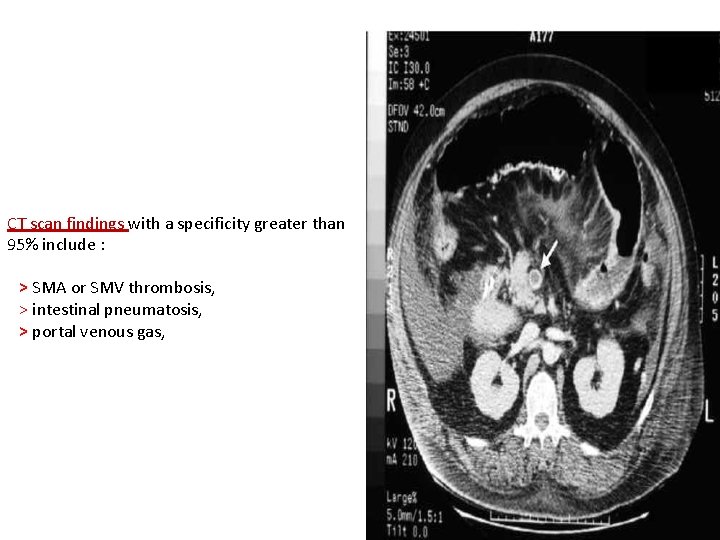

On plain films Late findings include > intramural air > air in the portal venous system. If bowel perforation occurs: > free air in the abdomen may be observed

CT scan findings with a specificity greater than 95% include : > SMA or SMV thrombosis, > intestinal pneumatosis, > portal venous gas,